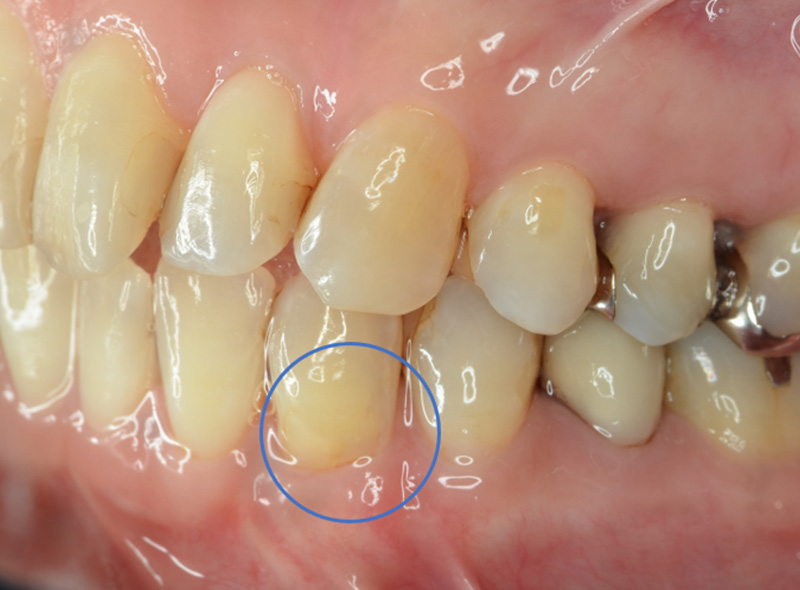

歯周形成外科 結合組織移植

エムドゲインによる歯周組織再生療法

Before

After

| 主訴 | 下の歯の歯肉が下がっていている |

|---|---|

| 治療期間 | 約1ヶ月 |

| 費用 | 120,000円 |

| デメリット・注意点 | 術後に腫れる可能性がある。 |